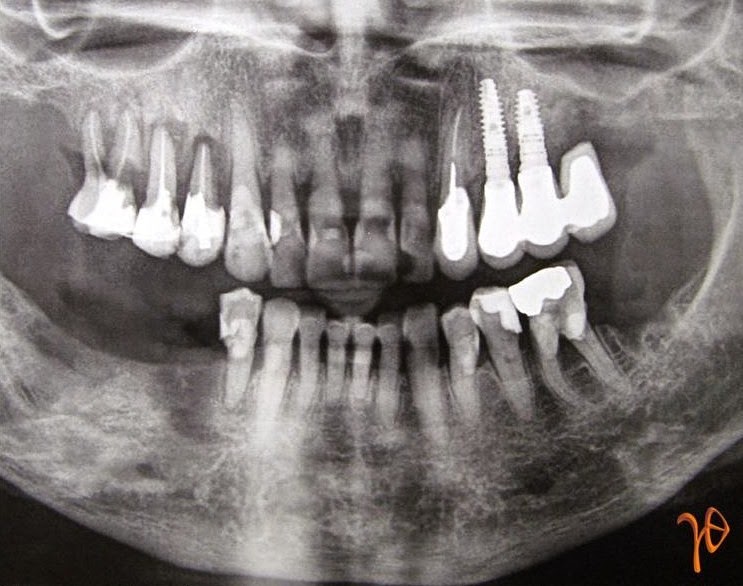

Η ασθενής, πριν την έναρξη της θεραπείας με Prolia, είχε υποβληθεί με επιτυχία σε τοποθέτηση οδοντικών εμφυτευμάτων στην άνω γνάθο, αριστερά(Εικόνα 1). Δεν είχε λάβει την δεύτερη δόση και 10 μήνες μετά την λήψη της πρώτης δόσης είχε υποβληθεί σε δύο εξαγωγές(#46, #37) χωρίς να εμφανίσει επιπλοκές.

Εικόνα 1. Πανοραμική Α/Α με τα οστεοενσωματωμένα οδοντικά εμφυτεύματα άνω αριστερά(βέλη), από την πρώτη προσέλευση της ασθενούς.